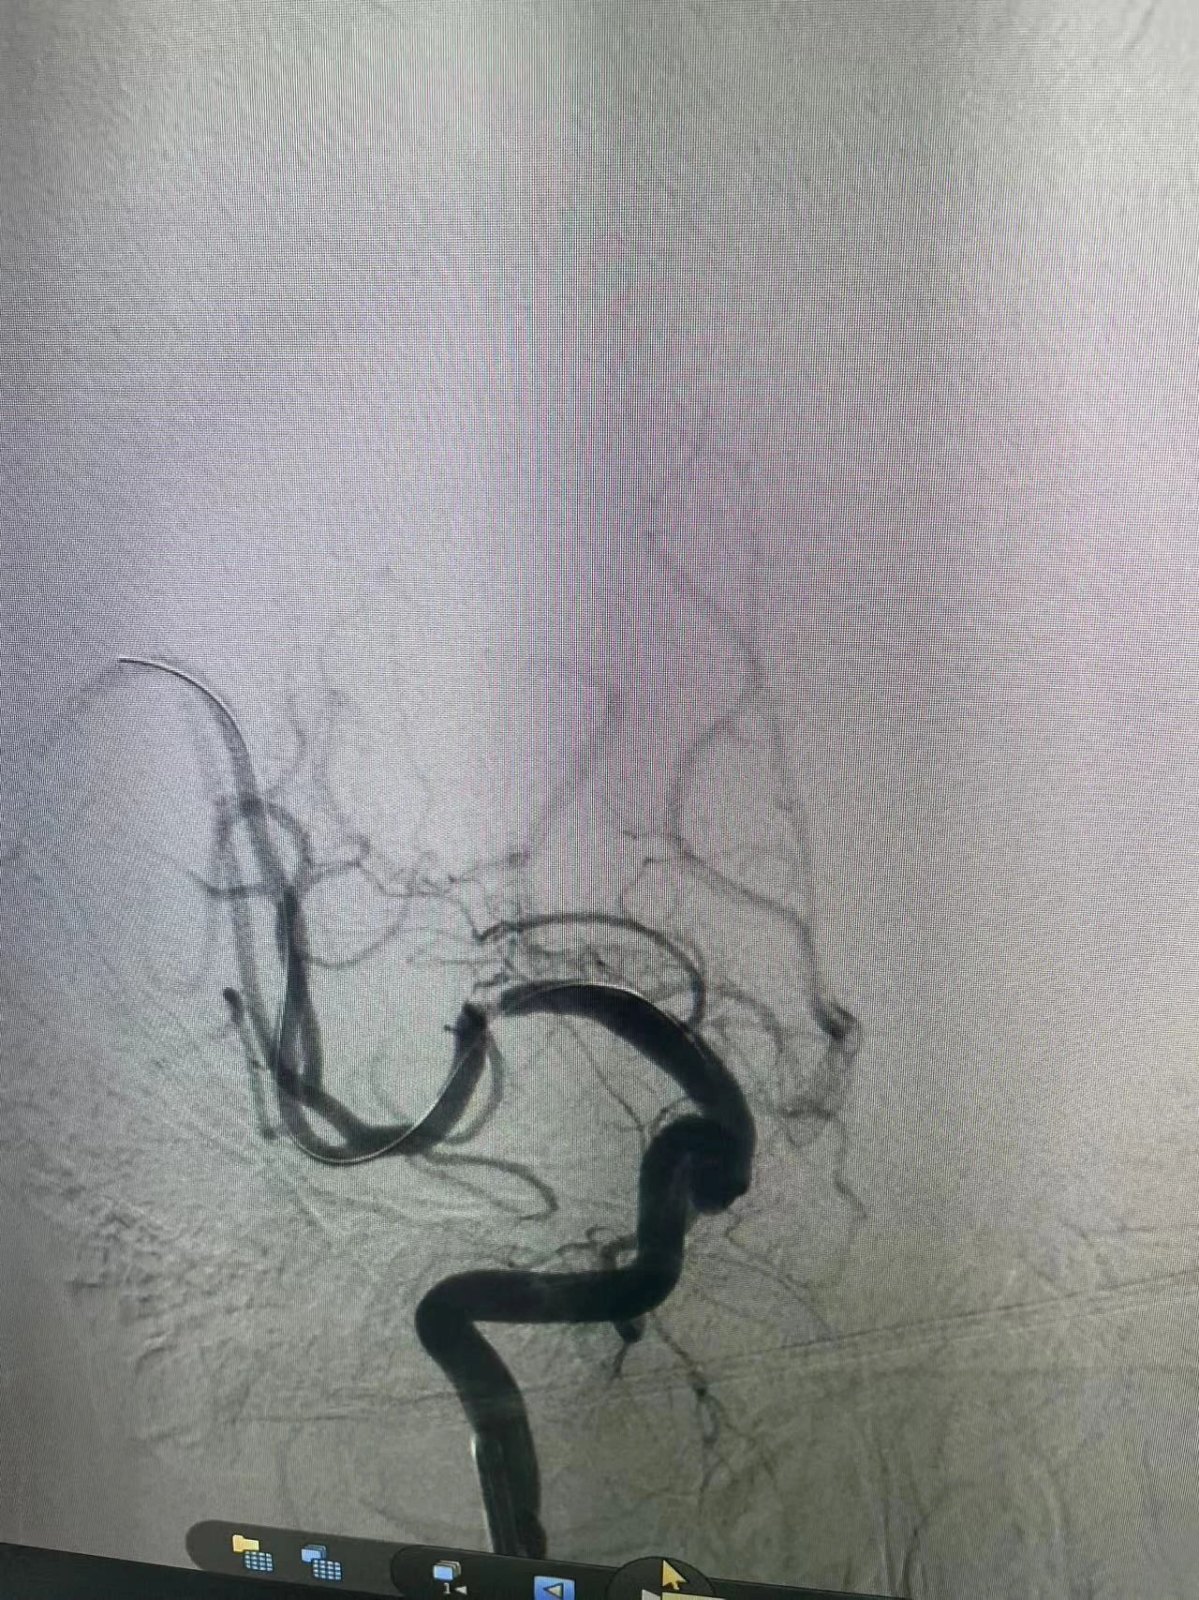

在导管室的无影灯下,一场与死神的较量悄然展开。家属的信任目光化作医者无畏的动力,造影剂显影瞬间印证了术前判断——右侧大脑中动脉完全闭塞。介入专家精准操控抽吸导管,成功取出新鲜血栓,然而复查造影显示血管仍存在重度狭窄。

"准备2.0/15mm球囊,立即行血管成形术!"随着导丝精准穿行,球囊在狭窄段完美展开。当造影剂再次流淌的刹那,原本淤滞的血管重现通畅,台上监护仪的波形跳动与患者的肢体活动同步恢复。